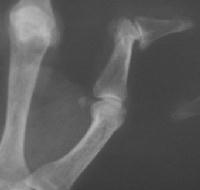

Unstable IP joint with a nodule on the exposed prominence of the proximal phalangeal head.